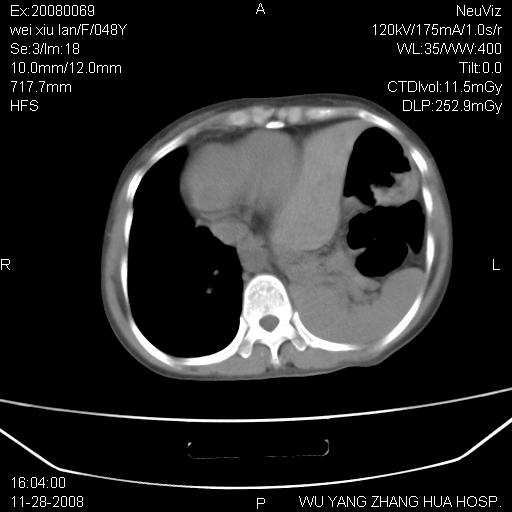

标题: CT16847:女,48岁,咳嗽,发热两日,平常偶有上腹部不适。 [打印本页]

标题: CT16847:女,48岁,咳嗽,发热两日,平常偶有上腹部不适。

能否考虑食管裂孔疝?请老师们多多指教。

这个是左侧膈膨升伴不完全性胃翻转,手术将松弛的左横膈膜折叠缝合即解决问题。

支持左侧膈疝,心脏受压右移.

胃、脾脏及部分肠管明显升高,并压迫心脏移位,

首先考虑:左侧膈疝。

左侧胸腔内见胃肠及脾脏影

支持膈疝

左膈顶及肋膈角均上移,膈面光滑,考虑左膈肌麻痹